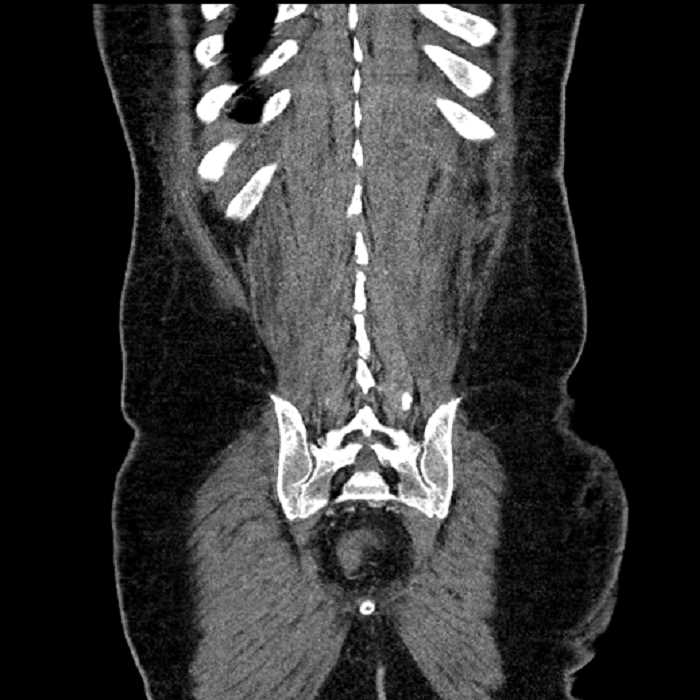

Age: 63

Sex: Male

Indication: Abdominal pain

• High grade stenosis of the left common iliac artery, with the left internal and external iliac arteries remaining patent

• Ankylosis of both sacroiliac joints

Acute sigmoid diverticulitis complicated by a small contained perforation and a large abscess in the right hepatic lobe. Additional small subcapsular abscesses along the anterior margin of the left hepatic lobe.

High grade stenosis of the left common iliac artery. The left external and internal iliac arteries are patent.